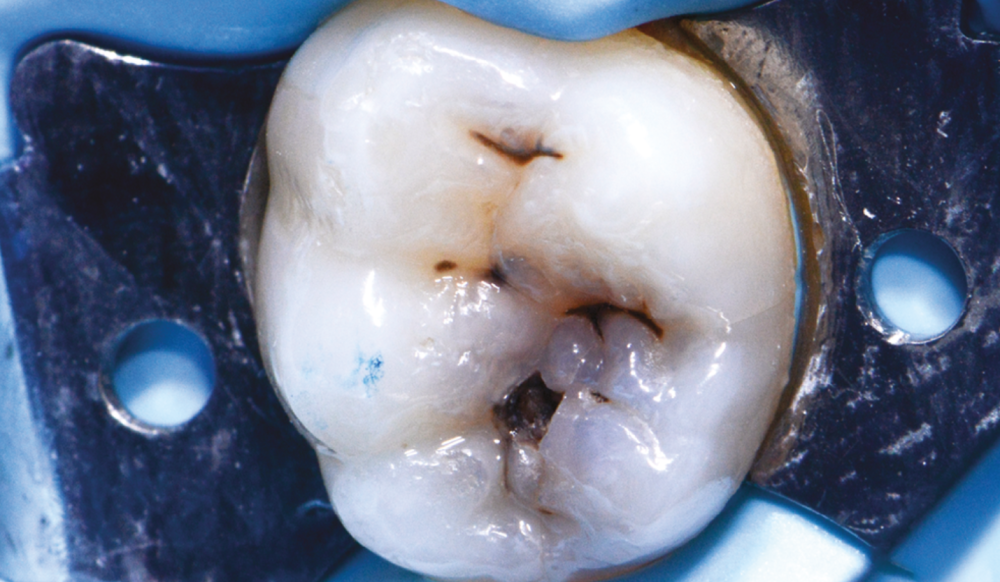

Saisie par l’Assurance maladie, la Haute autorité de santé (HAS) se prononce en faveur du remboursement de quatre actes dentaires mini-invasifs pour enrayer l’évolution des caries et préserver les tissus dentaires. Ces actes « permettent de préserver la dent sur le long terme et d’éviter des traitements traumatiques et coûteux », indique-t-elle le 11 décembre.

Trois actes conservateurs sont validés :

le traitement restaurateur atraumatique, qui consiste à éliminer la carie avec des instruments manuels (non rotatifs) avant d’obturer la cavité avec un matériau adhésif ;

le scellement thérapeutique, qui stoppe la progression d’une carie débutante par l’application d’un matériau fluide sans retrait préalable ;

la pulpotomie thérapeutique sur dent permanente mature, « assimilée à une dévitalisation partielle », avec retrait d’une partie de la pulpe et pose d’un biomatériau protecteur et régénérant. « Une alternative moins destructrice que les traitements endodontiques classiques », précise la HAS.